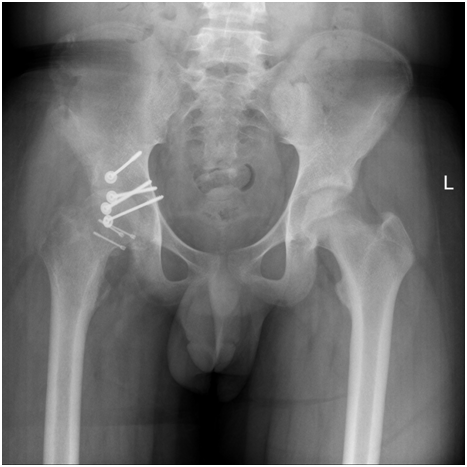

3. I did anterior approach to right iliac bone and full thickness graft 8 cm length and 4 cm width is taken-reconstruction of posterior wall of Acetabulum is done.

4. I have put inner concave cortex of graft towards head femur and shaving outer cortex to prevent impingement then fixation to posterior column of Acetabulum by 4 canulated screws 4mm-post fixation hip is stable in all direction and there is good cover of head femur-then skeletal traction to distal femur is done-closure in layers.

Figure 3 Neglected  recurrent fracture dislocation hip After 3 Months.